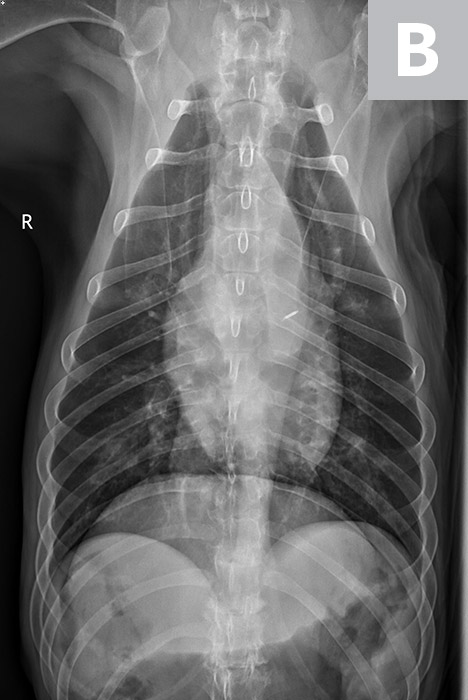

Serum chemistry profile and CBC results were normal, and heartworm antigen test results were negative. Thoracic radiography (right lateral, left lateral, ventrodorsal) revealed a diffuse bronchial pattern but was otherwise unremarkable with no cardiomegaly (vertebral left atrial size, 2.1 [normal, 1.4-2.2]; vertebral heart scale, 9 [normal, 8.7-10.7]) or observable airway collapse (Figure 1). Arterial blood gas showed partial pressure of arterial oxygen 97 mm Hg (normal, 81-103 mm Hg). Echocardiography revealed myxomatous mitral valve degeneration (B1) with no evidence of pulmonary hypertension.2 Laryngoscopy/bronchoscopy showed moderate mucosal irregularity and increased mucus of the lobar bronchi (Figure 2) with normal laryngeal function. Concurrent dynamic bronchial collapse of the left and right mainstem bronchi (grade II/III) was observed (Figure 3).3 Bronchoalveolar lavage was performed and submitted for cytologic evaluation and aerobic culture. Cytology revealed nonseptic neutrophilic inflammation (Figure 4); aerobic culture was negative.

FIGURE 1A

Thickening and mineralization of the airways characteristic of a bronchial pattern and suggestive of chronic airway inflammation